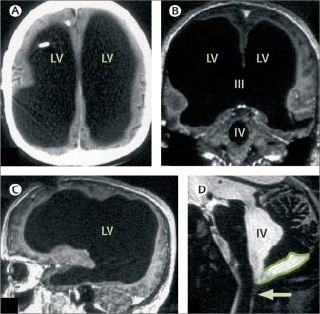

Brain of a white-collar worker

Feuillet et al., 2007